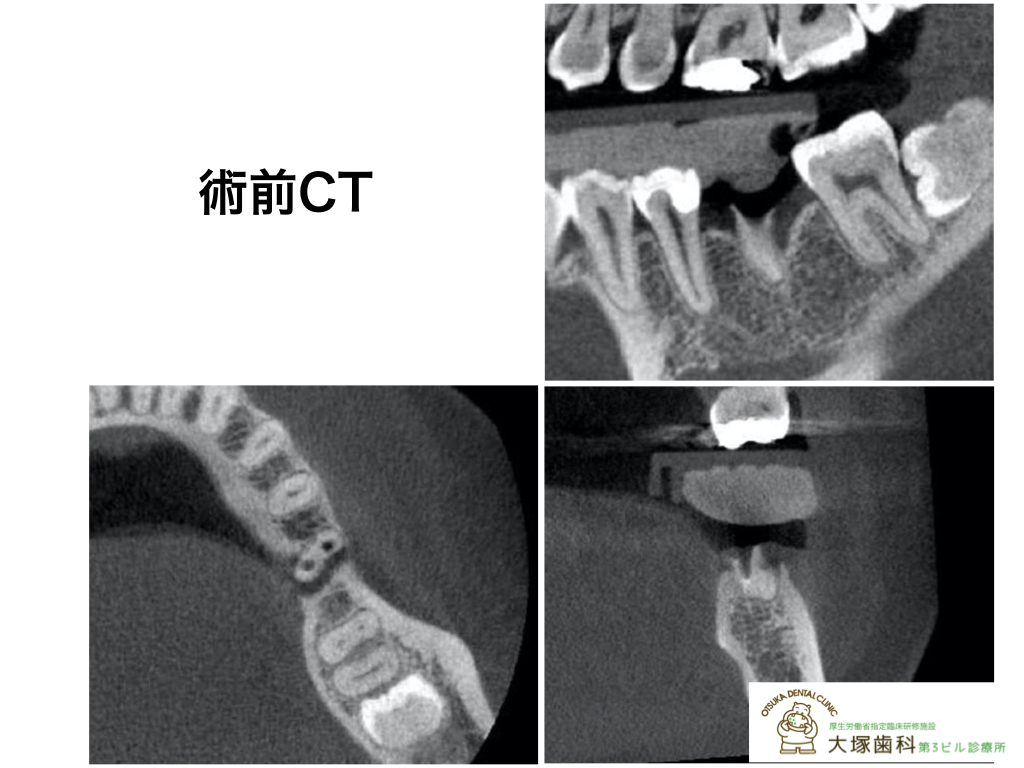

[レントゲン術前]

[レントゲン術後]

[レントゲン術前]

[レントゲン術後]